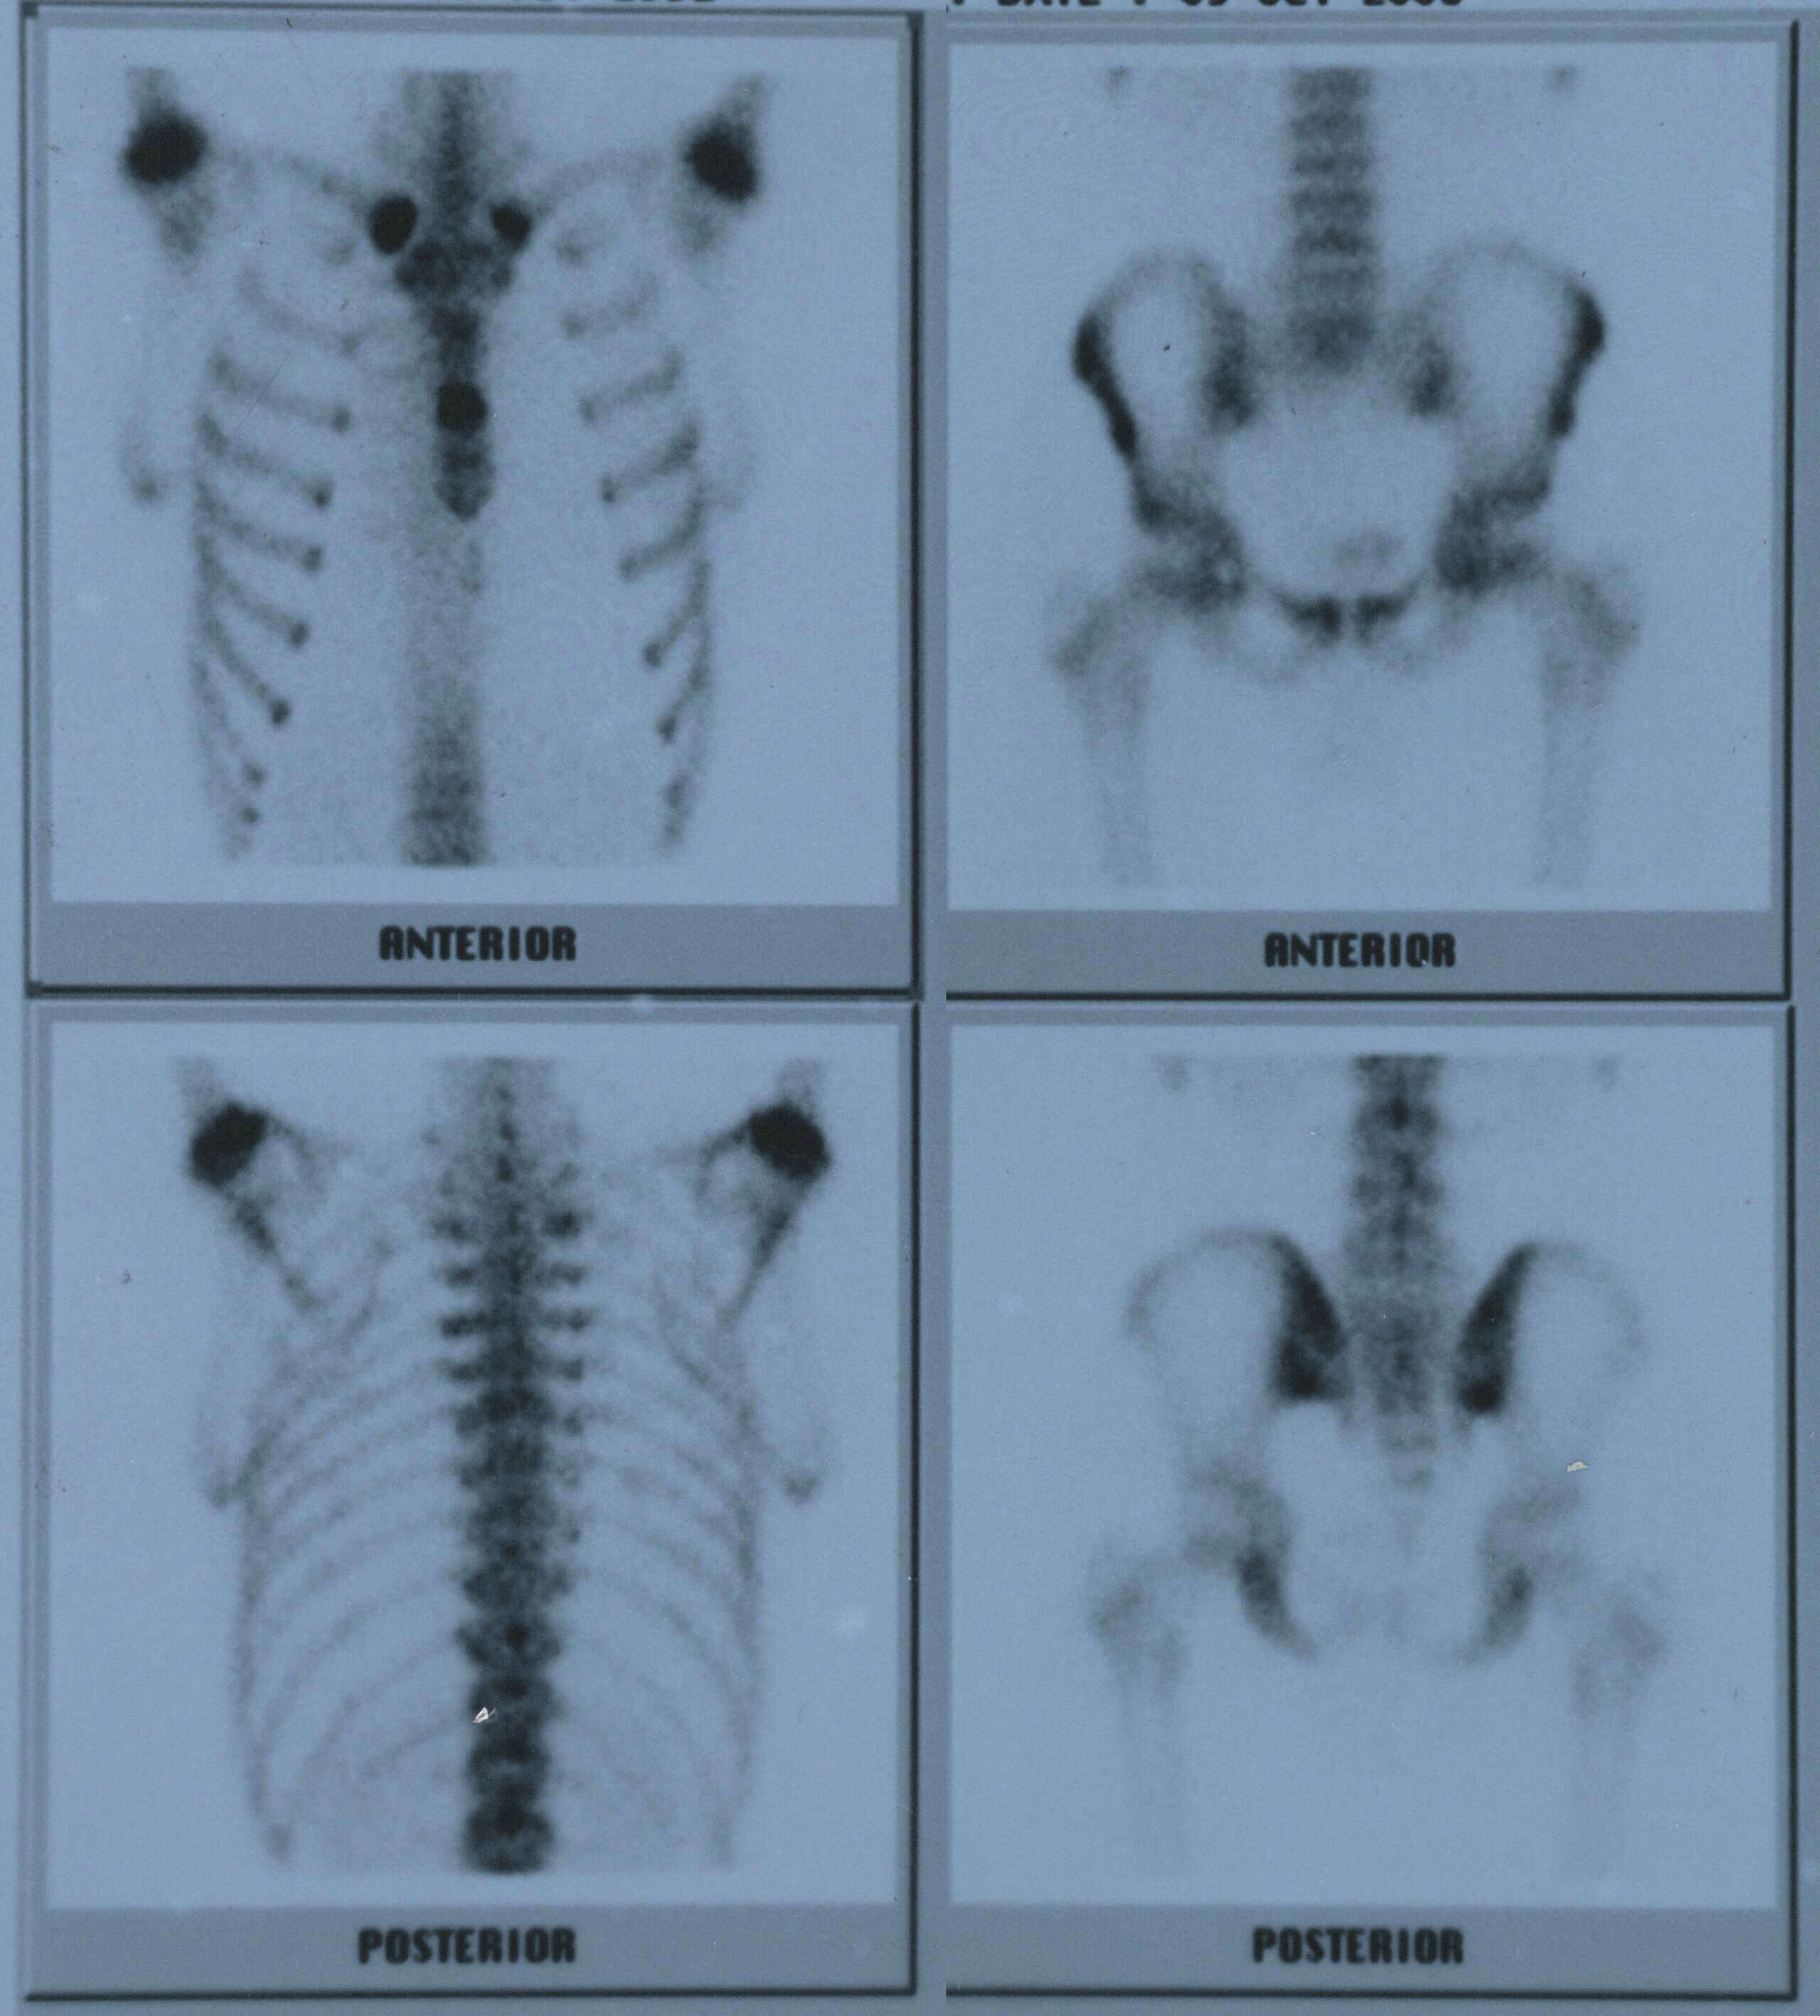

Liver and renal function tests were normal. The erythrocyte sedimentation rate (ESR) and C- reactive protein (CRP) were 69 mm/1sthour (range 0-20) and 2.8 mg/dl (range 0-0.8), respectively. HLA B27 level was positive. To exclude septic arthritis Magnetic Resonance Imaging (MRI) of the sacroiliac joint was performed which revealed bilateral, symmetrical sacroiliitis as a possible inflammatory arthritis but no findings associated with septic arthritis (Figure 2). So, SAPHO Syndrome was considered and to diagnose whole body Tc 99m-MDP bone scintigraphy was studied which showed increased uptake on chest wall, corpus sterni and bilateral sternoclavicular joints. This is known as "bull's head" or "bull-horn" sign and is characteristic for SAPHO [7] [8] (Figure 3). As a result, a diagnosis of SAPHO Syndrome was made.

Figure 3: Increased Tc-99m uptake in bone scintigraphy and bull's head sign in right upper one.